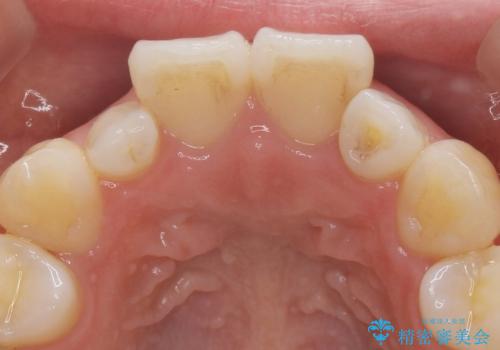

全顎的に歯並びにがたつきがあり、上の側切歯(上顎両側2)は生まれつき小さい歯(矮小歯)でした。

矯正治療後、矮小歯をセラミッククラウンにより理想的な歯の大きさに仕上げました。

クラウンの種類:オールセラミッククラウン スペシャル